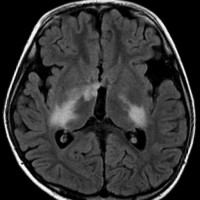

幼児の視路の毛様粘液性星細胞腫です。T2強調画像(左側)で白く高信号に写るのが特徴です。ガドリニウム増強ではまだらになっていますが,均一に真っ白に高信号になることも多いです。乳幼児のものは,ドロドロに柔らかい腫瘍です。

whole optic pathway pilocytic astrocytomaとは

両側の眼窩内視神経から視交叉、視索,外側膝状体,内包後脚,視放線近位部までが腫瘍化しています。FLAIRで高信号で,不規則にガドリニウム増強されます。これを手術摘出したり生検したりしても無駄です。放射線治療は不可能であり治療方法は化学療法のみです。